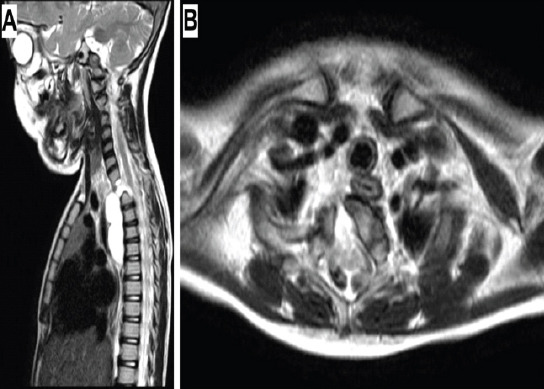

Case report: A 4-year-old boy was referred to our spine surgery unit for the evaluation and management of an incidentally detected T1 vertebral anomaly. Magnetic resonance imaging revealed the presence of a focal defect over the right half of the T1 vertebral body, through which herniation of a fluid-filled sac into the pre- and right paravertebral regions was noted. A diagnosis of anterior thoracic meningocele was made, and surgery was advised. Following surgical exposure of the entire extent of the sac, needle aspiration to decompress the lesion was performed, which yielded a milky-colored viscous fluid, unlike cerebrospinal fluid. The likelihood of an enterogenous cyst was suspected. The lesion was excised at the level of the base of its peduncle, and the vertebral defect was closed using a small contoured plate. Histopathologic evaluation confirmed the presence of an enterogenous cyst.